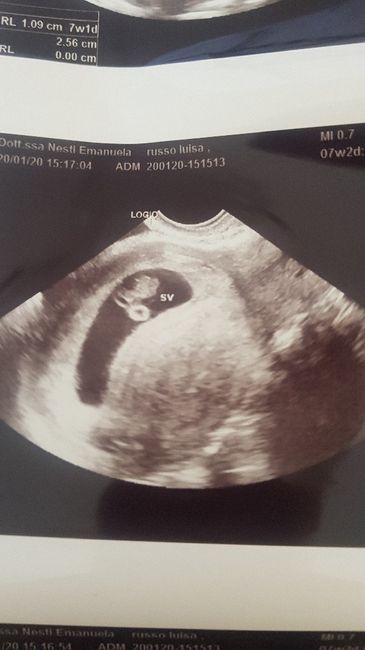

Metodo Ramzi! Chi ci sa azzeccare? 5

Metodo Ramzi! Chi ci sa azzeccare? 6

Ciao ragazze, qualcuna esperta del metodo mi può dire cosa ne pensa? La prima è di 7+2 e la seconda 8+4 entrambe interne... Grazie mille 😘